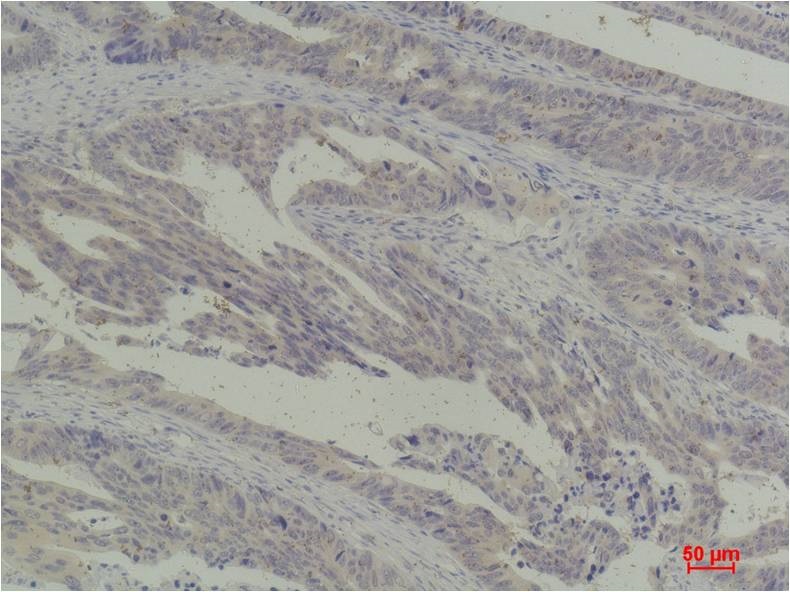

Immunohistochemical analysis of paraffin-embedded Human Breast Carcinoma using c-Jun(BE3427)Rabbit pAb diluted at 1:200